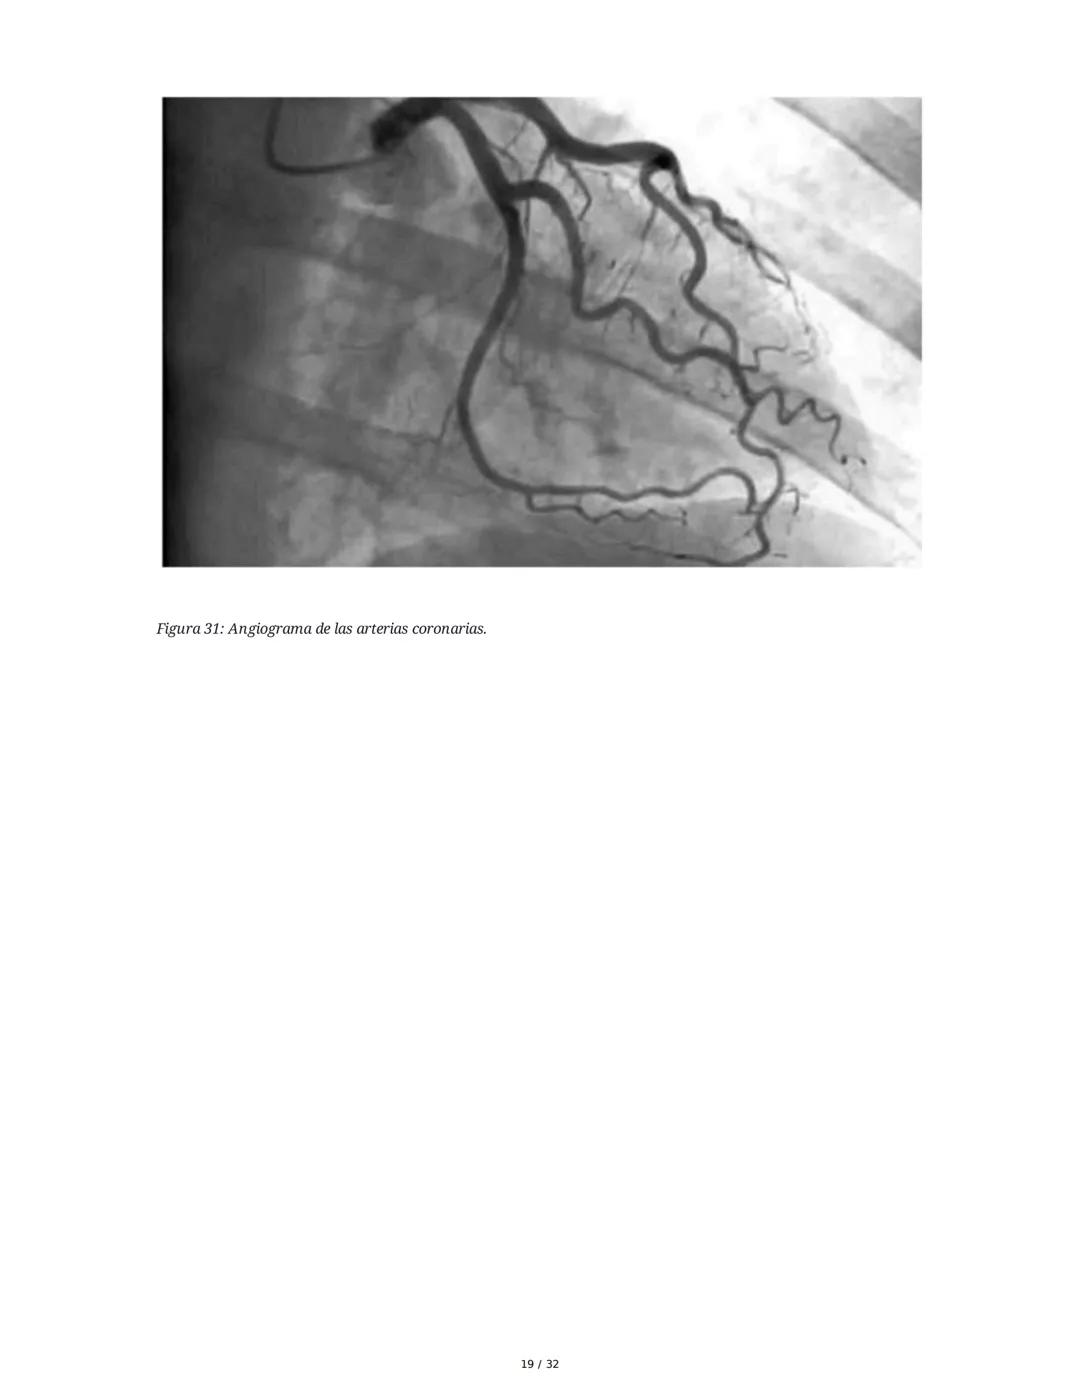

Estudios complementarios: La ecocardiografía evalúa la función cardíaca, mientras que la coronariografía permite visualizar directamente las arterias coronarias mediante contraste.